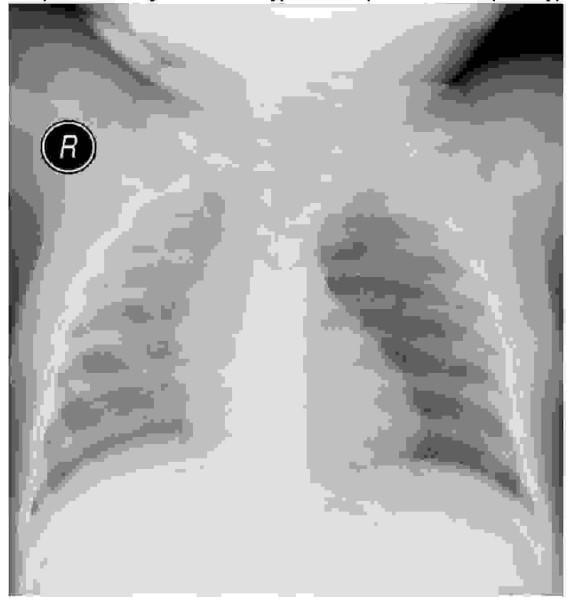

U niechorującego dotychczas 2,5-letniego chłopca nastąpiło bardzo gwałtowne pogorszenie stanu klinicznego (w tym wystąpienie duszności) w trakcie wirusowej infekcji górnych dróg oddechowych. W udziale zamieszczonego RTG klatki piersiowej ustal wstępne rozpoznanie i postępowanie:

Pytanie 17